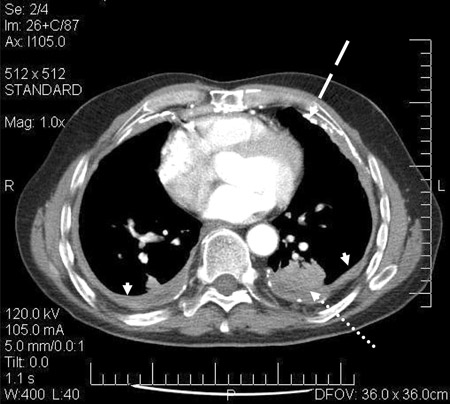

CT scan confirming symmetrical thickening (arrowheads) with a calcified pleural plaque (broken arrow, top right) and an area of rounded atelectasis (Blesovsky's sign; dotted arrow, bottom right)

Adapted from BMJ Case Reports 2009; doi:10.1136/bcr.06.2008.0253